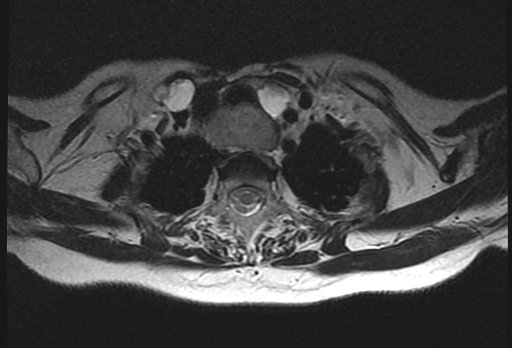

Магнитно-резонансная томография (МРТ) позволяет получить детальную топографо-анатомическую картину опухоли и ее соотношение с органами и структурами шеи. Это необходимо при планировании хирургического лечения в случае инвазии опухоли в соседние структуры.